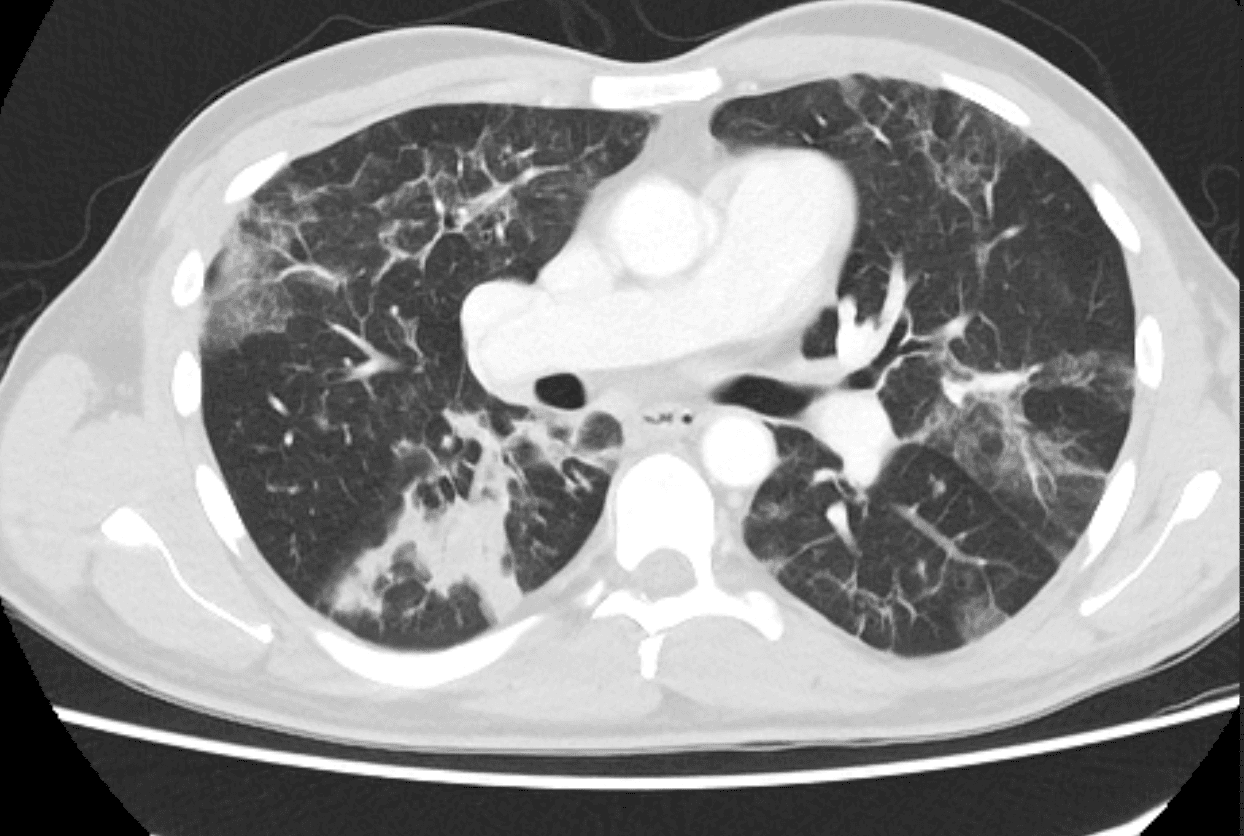

Laboratory studies show white blood cell count 12.6 x 10^3/uL with 14% eosinophils, absolute eosinophil count 1.8 x 10^3/uL, creatinine 1.6 mg/dL near baseline, creatine kinase 78 U/L, and C-reactive protein 84 mg/L. Two sets of blood cultures remain negative, respiratory viral polymerase chain reaction testing is negative, sputum Gram stain shows mixed upper respiratory flora, and serum beta-D-glucan is not detected. Chest CT demonstrates new bilateral peripheral ground-glass and consolidative opacities. Bronchoscopy is performed because of worsening hypoxemia despite empiric cefepime and vancomycin; bronchoalveolar lavage cultures are negative, and the lavage differential shows 32% eosinophils.

CT chest demonstrating new bilateral ground-glass and consolidative pulmonary opacities.